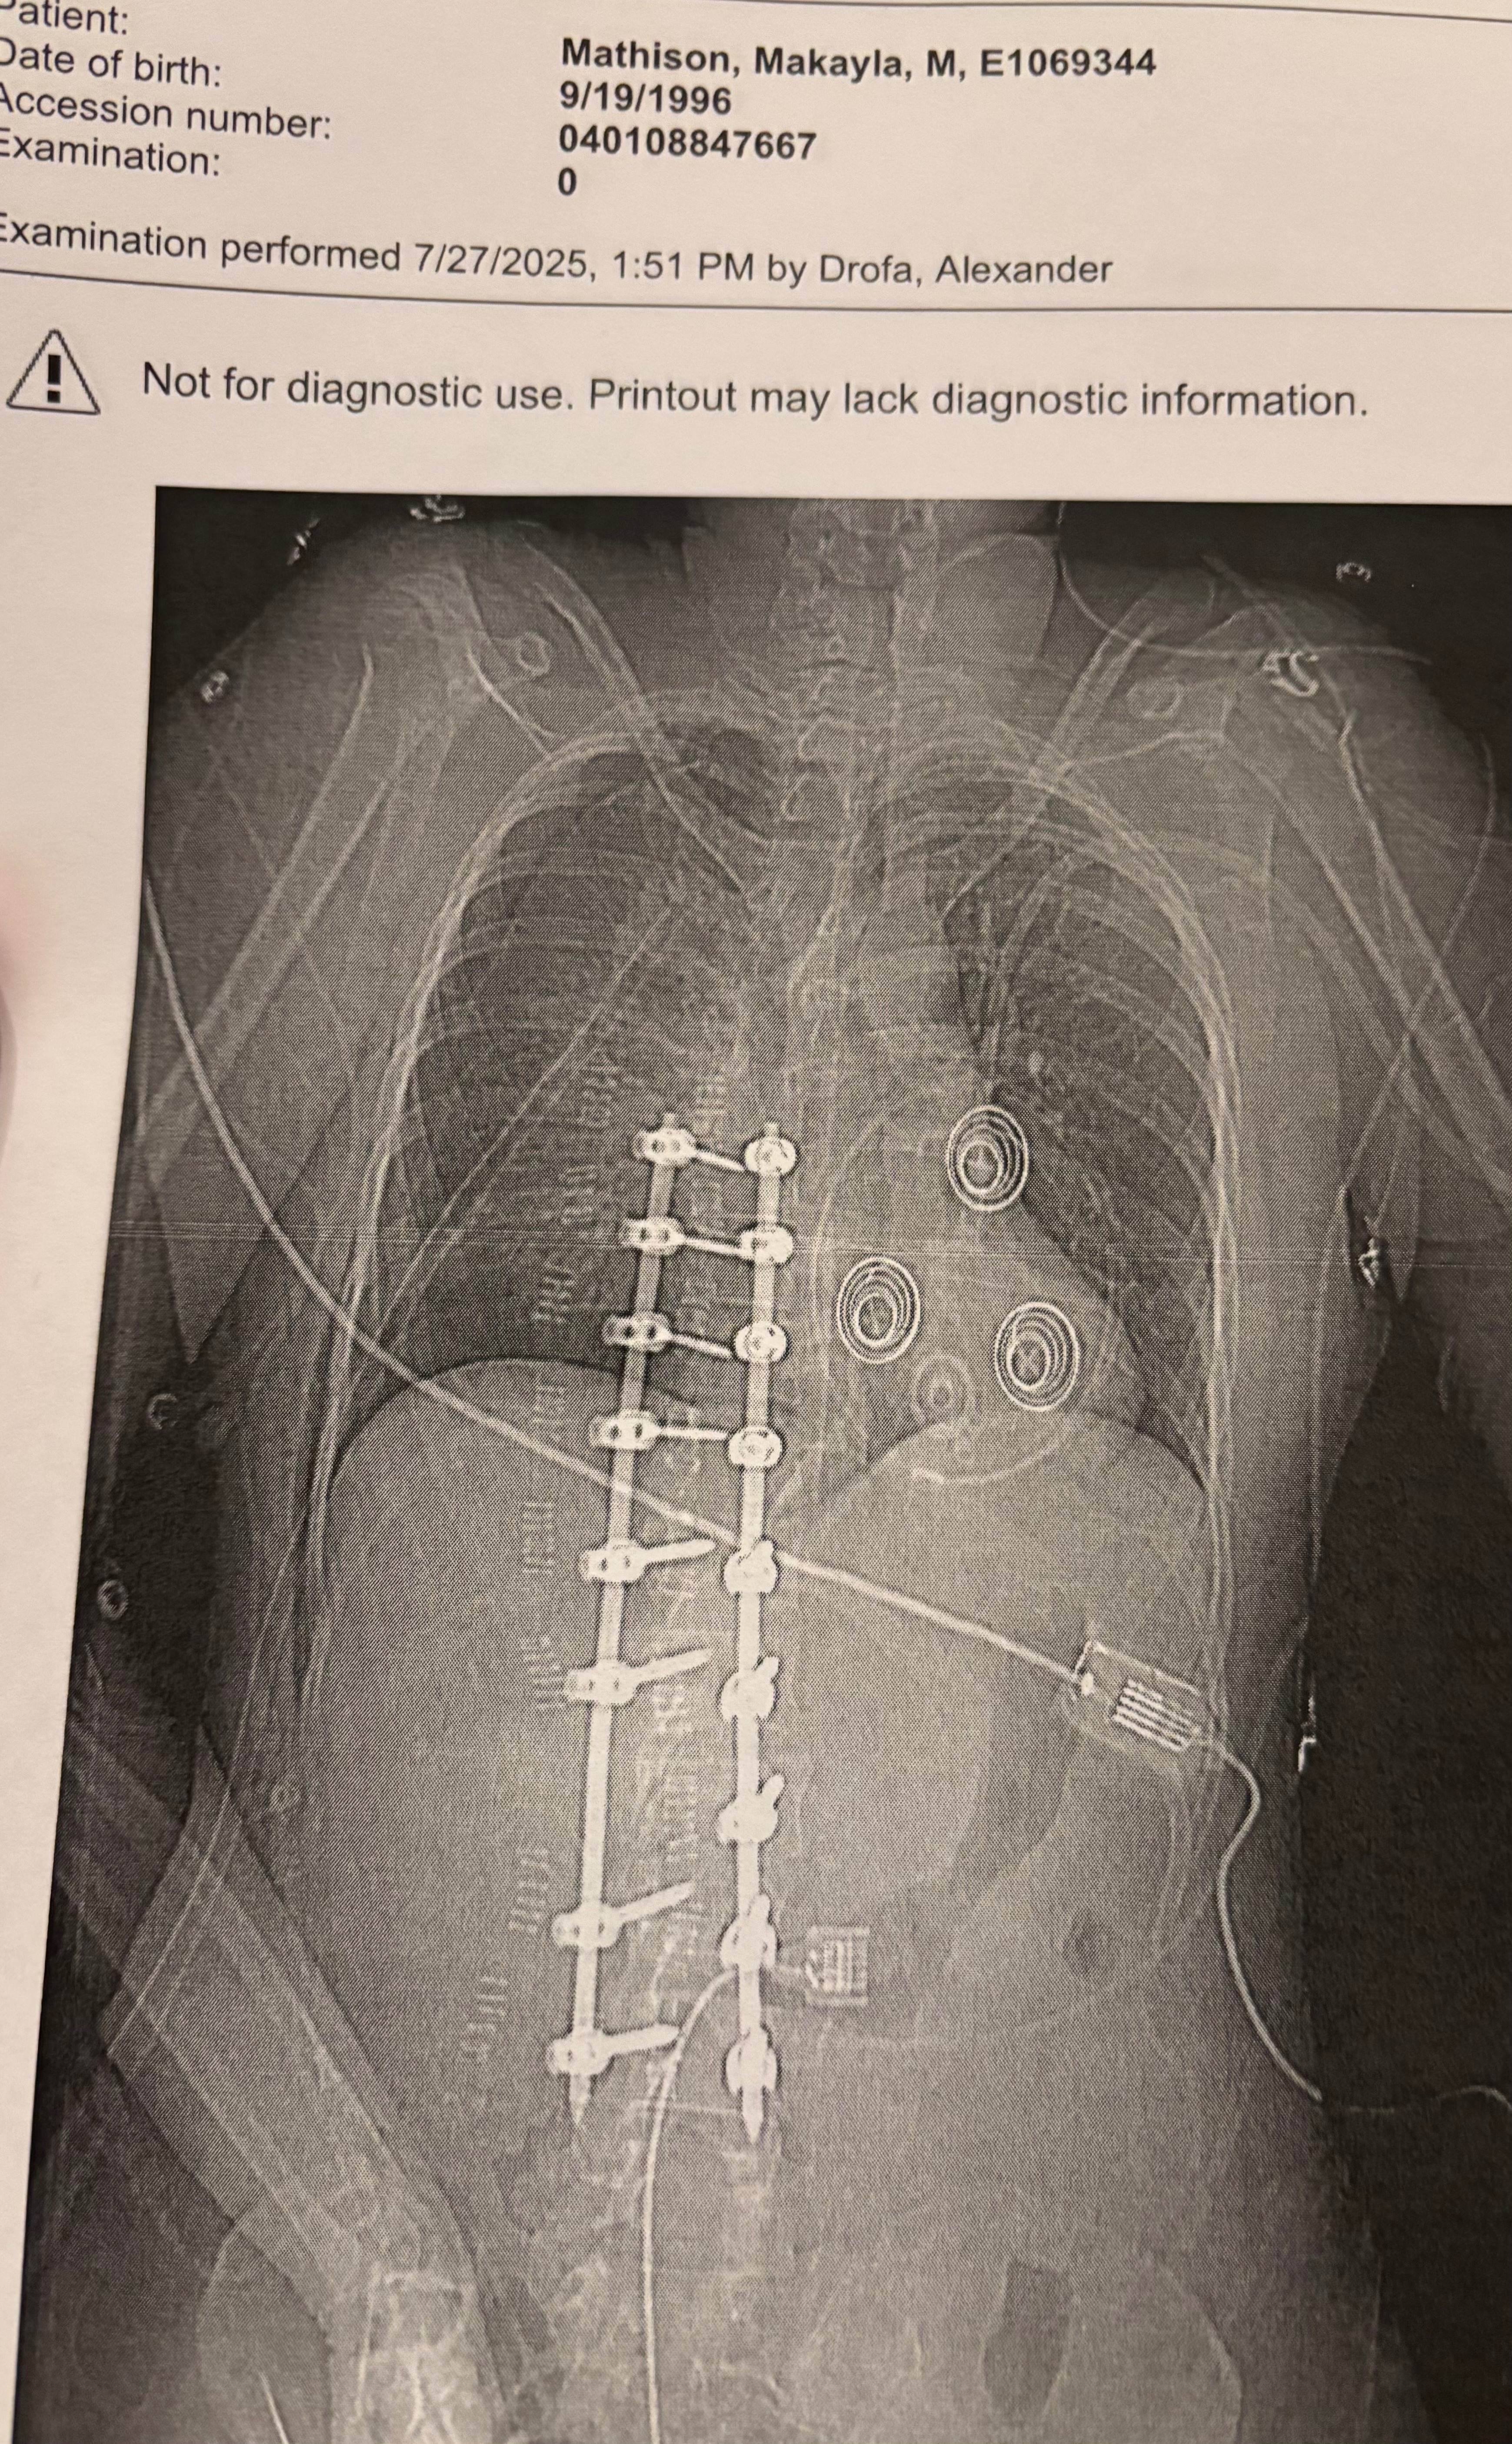

I was rushed to the hospital in Sisseton, SD, and immediately life-flighted to Fargo, ND, where I underwent emergency surgeries. The injuries were catastrophic. I had broken my L2 and T10 vertebrae and torn my dermal cord, which caused spinal fluid to leak dangerously. Doctors had to place a drain in my back, perform spinal fusion surgery, and insert rods to stabilize my spine & leaving me with 122 staples down my back.

That wasn’t all. My left hip and femur was broken. My sternum was fractured. A large portion of my ribs were shattered. One of my lungs collapsed and had to be partially removed. A chest tube was inserted just so I could breathe.

Today, I am considered half-paraplegic. I cannot walk, YET. I’ve been in the hospital for 12 days now, and the doctors say my recovery will be long and uncertain. I’ll need to be transferred to a rehabilitation center for weeks, maybe months, of therapy just to try and regain movement.